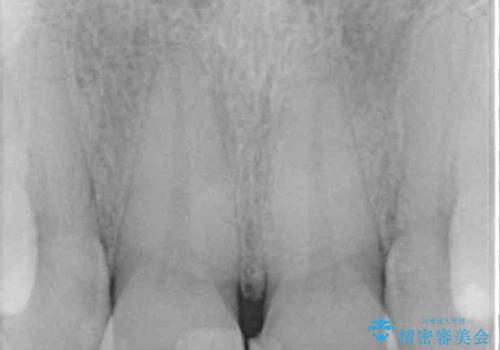

- 上顎2前歯の色を気にして来院された患者様です。

2本ともに虫歯治療による充填材の変色などによりつぎはぎのような前歯となっていたため、オールセラミッククラウンにて補綴治療を行うこととしました。